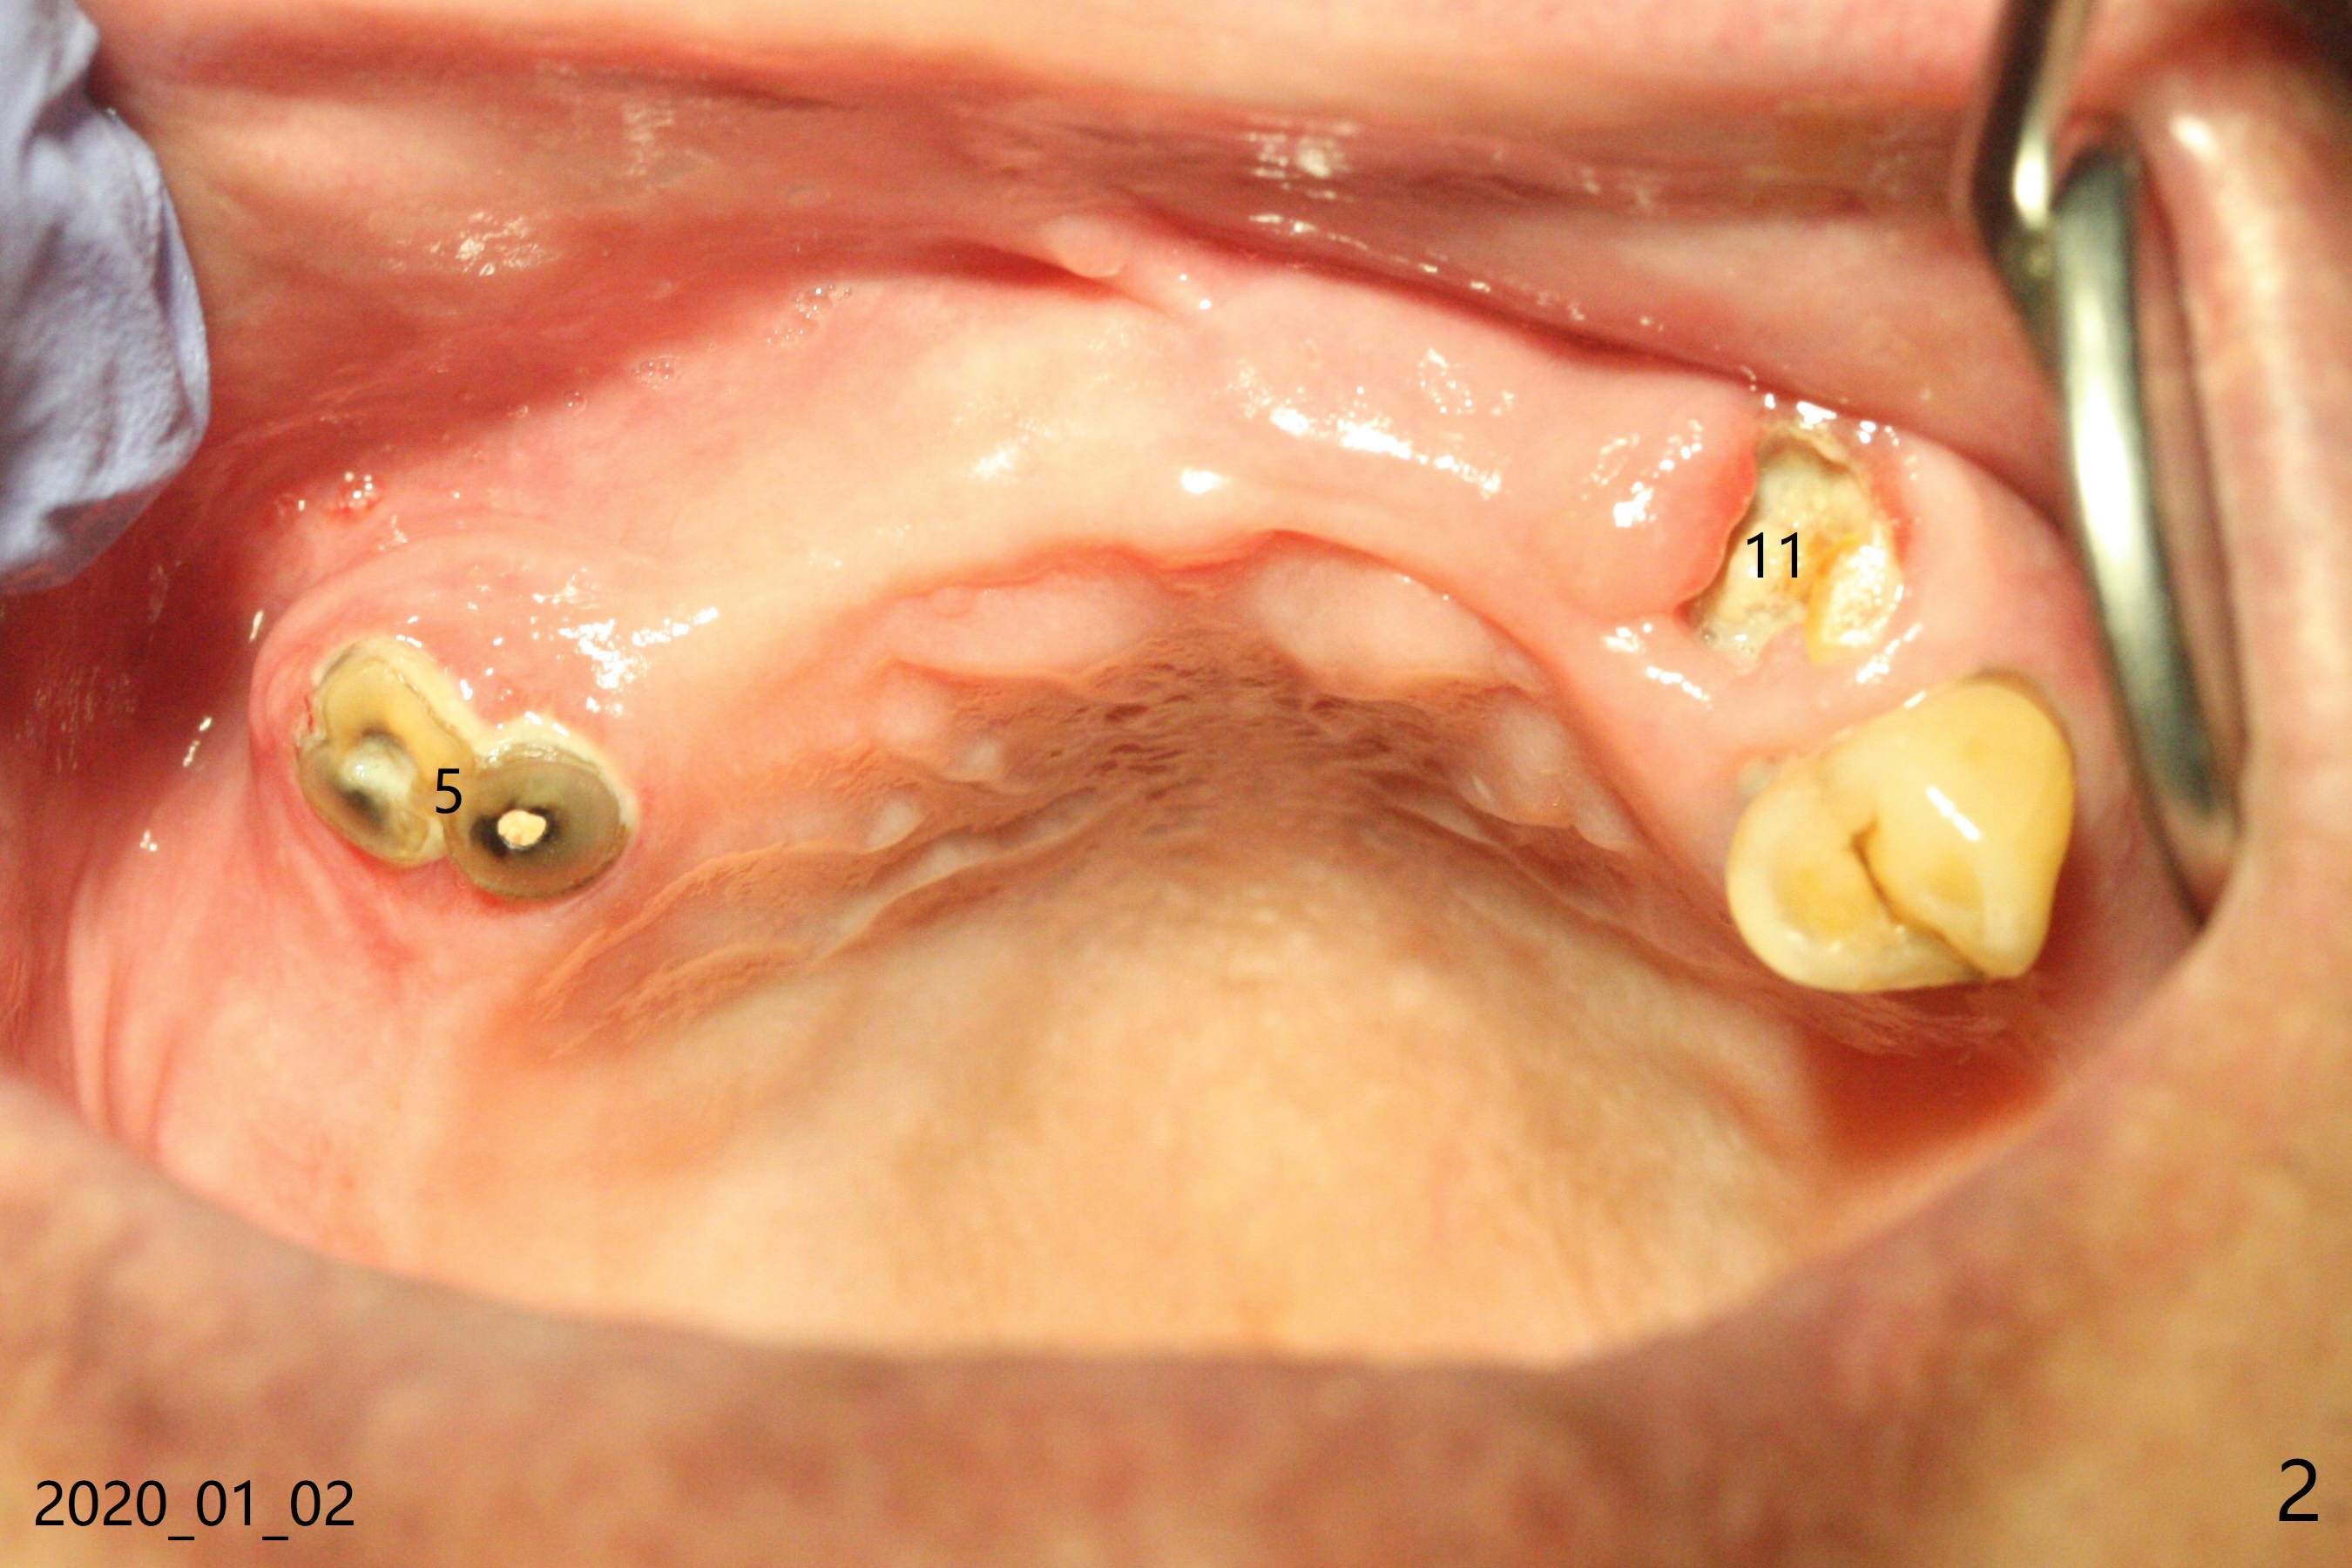

A 81-year-old man with upper and lower RPDs (Fig.1) requests extraction of the tooth #11 (Fig.2,3). After discussion, he agrees with socket preservation using Osteogen plug (Fig.4 O). The density at #11 is in fact higher than the neighboring healed socket (#10). Due to failure to transfer the flap to cover the socket and poor oral hygiene, the wound does not heal as well as expected 13 days postop (Fig.5).